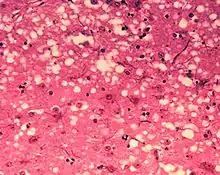

D'un point de vue anatomopathologique, on observe ainsi au niveau de l'encéphale la formation de vacuoles (donnant un aspect spongieux au cerveau, d'où le nom de spongiforme dans EST), une mort des neurones, une gliose (multiplication des astrocytes et de la microglie) et l'accumulation d'une protéine de l'hôte, la PrPC (abréviation de protéine prion cellulaire, l'isoforme normale), sous une conformation anormale (ou mal repliée) alors dénommée PrPSc (abréviation de protéine prion de la scrapie)[6].

- La mise en évidence d'une triade de signes neuropathologiques (perte neuronale, astrogliose, vacuoles spongiformes) ;